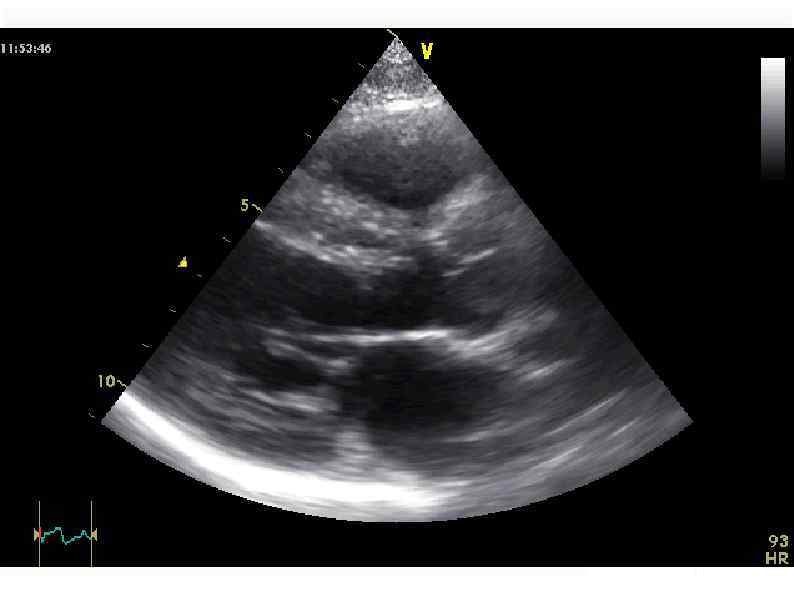

Эхо-КГ 16/09/11 (ЧСС - 140 -150/мин!) Диффузный гипокинез стенок левого желудочка, ФВ 55%. Митральная Эхо-КГ 16/09/11 (ЧСС - 140 -150/мин!) Диффузный гипокинез стенок левого желудочка, ФВ 55%. Митральная регургитация II степени, трикуспидальная регургитация II степени. Признаков легочной гипертензии нет.

Эхо-КГ 19/09/11 Эхо-КГ 19/09/11

Эхо-КГ 21/09/11 Эхо-КГ 21/09/11

Эхо-кг 2/10/11 При сравнении с предыдущим исследованием отмечается заметная положительная динамика в виде уменьшения Эхо-кг 2/10/11 При сравнении с предыдущим исследованием отмечается заметная положительная динамика в виде уменьшения размеров левого желудочка и улучшения сократительной функции